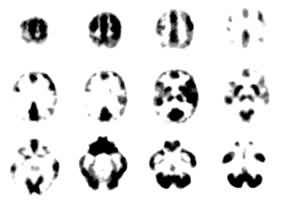

图 局部脑能量代谢显像

葡萄糖是脑组织唯一的能量来源物质,利用18F标记的脱氧葡萄糖(18F-FDG)和15O2作为示踪剂进行脑断层显像(图2),从影像上各部位提取出18F和15O的数量信息,代入生理数学模型可以计算出脑组织各部位的葡萄糖代谢率(LCMRGlu)和氧耗量,计算值以不同的色阶显示在相应部位,构成一幅代谢影像。由于18F和15O是正电子发射体,需用能探测正电子湮没辐射后产生的成对γ射线的专用仪器──正电发射断层照相机(PET)。这种仪器和生产18F、15O等正电子发射体所需的加速器价格昂贵,技术较为复杂,故本检查目前尚不能作为临床常规使用,多用于脑神经精神活动研究。本法已成功地应用于研究特定神经核团作功与外界刺激的应答关系,如听语言时左颞叶听觉皮层的葡萄糖代谢率明显增高,听音乐则在右侧听觉皮层葡萄糖代谢率增高。用本法也成功地观察到精神分裂症和抑郁症抑郁期患者的额叶皮质有明显的葡萄糖代谢率减低,用药物增进该区的代谢率,临床症状随之改善。因此,科学界认为本法将在21世纪揭示人脑功能和精神疾病秘密的伟大研究中作出重大贡献。